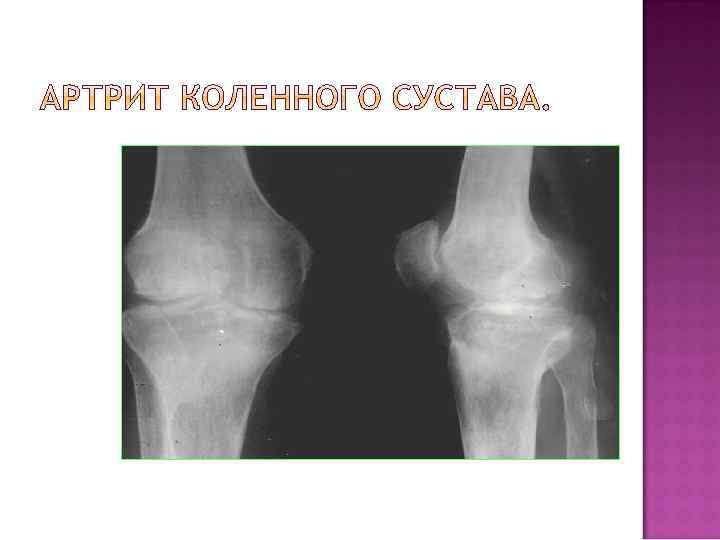

Нарушения развития костно-суставного аппарата Травматические повреждения и их последствия Воспалительные процессы Дегенеративно-дистрофические поражения Нейродистрофические Нарушения развития костно-суставного аппарата Травматические повреждения и их последствия Воспалительные процессы Дегенеративно-дистрофические поражения Нейродистрофические поражения Ретикулоэндотелиозы и невоспалительные гранулемы Поражения типа фиброзной остеодистрофии Опухолевидные образования и доброкачественные опухоли Злокачественные опухоли